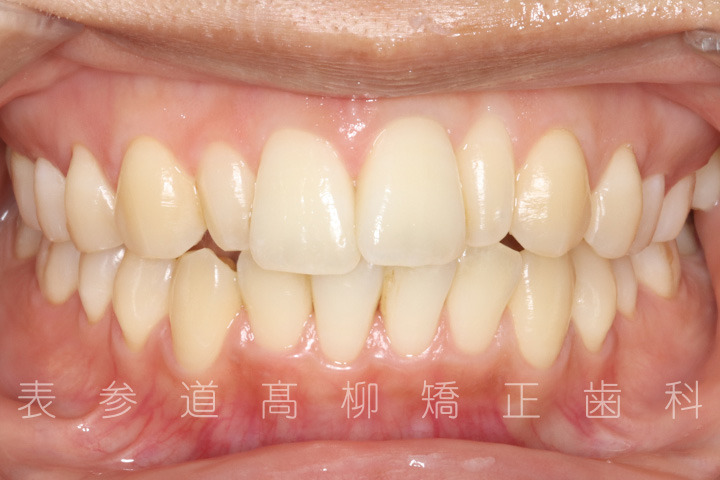

上の前歯が出ているのと前歯が小さいことをお悩みの患者様の症例をご紹介いたします。

治療前→治療後

術前術後の比較